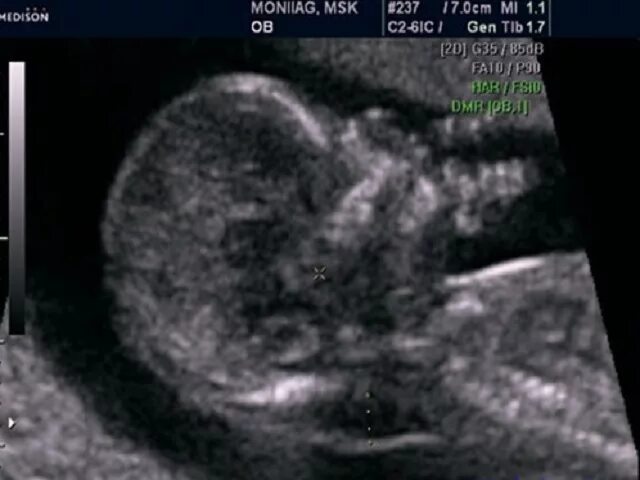

Узи аномалий